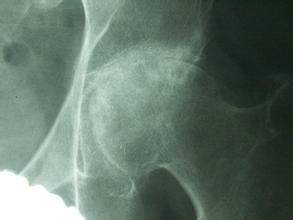

生活中如何调理股骨头坏死?股骨头坏死是一种很常见的疾病,患上股骨头坏死对我们简直就是一种噩梦,那么现实生活中我们又如何在家调理呢?又该怎样调理呢?下面由我院骨科专家为大家推荐一种有效的家中调理的按摩办法。》》》百看不如一问,咨询专家如何对症治疗

生活中如何调理股骨头坏死?股骨头坏死的按摩如下: